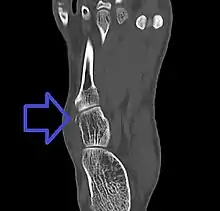

Avulsion fracture of the cuboid on CT